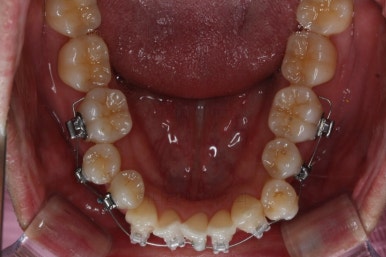

아랫니를 계속 당겨주면서 가지런하게 하고 있어요.

어느 정도 진행이 되었다 싶으면 윗니도 장치를 부착해서 가지런하게 해줘요.

윗니도 장치를 부착했어요.

아랫니보다 해야 할 작업이 많지 않기 때문에 이렇게 시간차를 두어 진행을 했고, 이렇게 하면 교정장치가 눈에 띄는 기간이 줄어들어 환자분의 만족도는 더 올라가게 되죠.

아랫니 이 뽑은 자리는 거의 다 다물렸어요.

거꾸로 물리는 앞니도 어느 정도 많이 개선이 되었고요.

화살표는 사랑니인데요. 이 분의 경우 아래 앞니가 1개 없고, 1개를 추가로 뽑아서 윗니 대비 아랫니가 총 2개 모자란거죠.

운이 좋게도 이 분은 사랑니까지 잘 나와있던 상태라 내버려두기 아까워 함께 가지런하게 해주고 사용하실 수 있게 해드렸어요.